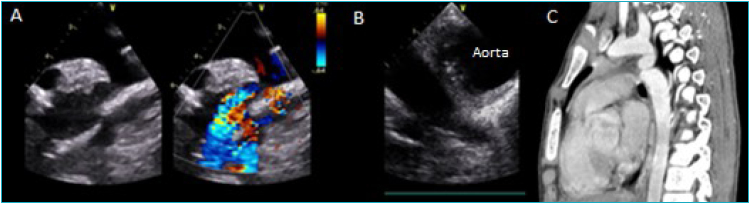

Case description: Two male patients aged 13 and 9 years old were admitted. The first due to a fever for 2 months, which started after dental cleaning, and the second due to high blood pressure, both patients with asthenia and weight loss. In the first case, the transthoracic echocardiogram showed aortic coarctation, and the transesophageal echocardiogram showed the presence of vegetations in the post-coarctation area, without pseudoaneurysms, with blood culture positive for Streptococcus mitis. This patient was treated for six weeks with crystalline penicillin, resolving the infection without complications. The second case was assessed for high blood pressure with a history of fever, and was treated with antibiotics. When performing a transthoracic echocardiogram, aortic coarctation was observed with a saccular image classified as a pseudoaneurysm by angiography and tomography. Blood culture was negative, and the patient developed an episode of hematemesis whose initial etiology could not be determined. Before surgical repair, he had a second episode of copious hematemesis with hypovolemic shock and death.